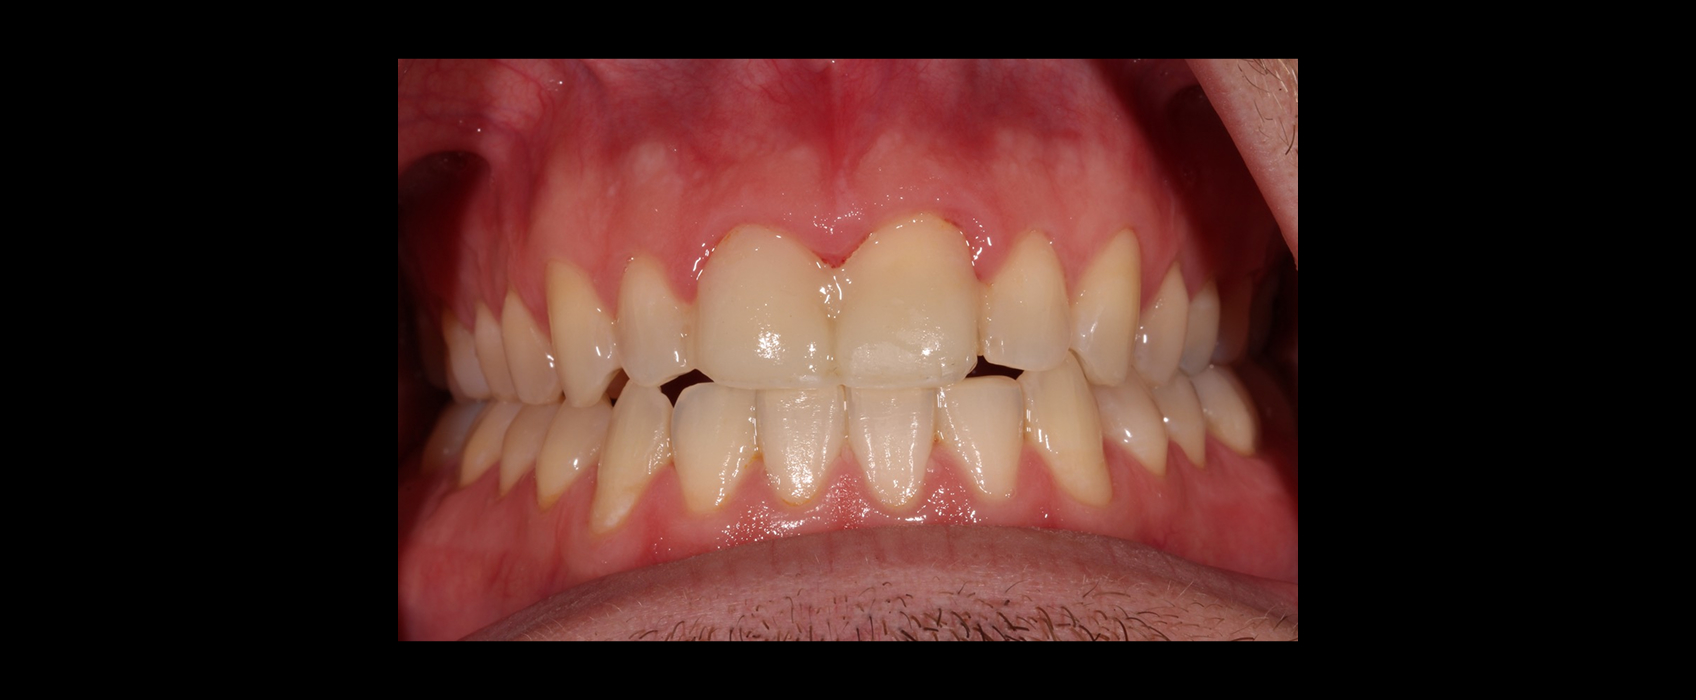

Clear aligners with attachments and elastics were used to correct the crossbite and improve tooth position. After 18 months, Zach’s teeth were in an ideal position for restorative care.

With the attachments removed, we prepared #8 and #9 and placed a diagnostic provisional to test esthetics and function. After one month with no occlusal adjustments needed, we moved forward with the definitive porcelain restorations.